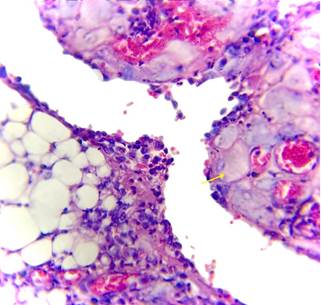

Microscopically,

the fibroadipose tissue was composed predominantly of mature adipocytes with

mild chronic inflammatory cell infiltrates. The submesothelial regions revealed

decidual cells arranged singly as well as in small focal nodular clusters.

These cells were large and polygonal, with abundant finely granular

eosinophilic cytoplasm. Their nuclei were round, bland, and contained a single

prominent nucleolus, without atypical features such as pleomorphism,

hyperchromasia, or increased mitotic activity (Figure 2). Importantly, no

epithelioid cell granulomas were identified, thereby excluding granulomatous

inflammation.

Figure 2. (H&E,

10X)Sections showing decidual tissue invading the peritoneal tissue. A decidual

cells is seen with abundant eosinophilic cytoplasm and round to oval nucleus

and vesicular chromatin (Yellow arrow).